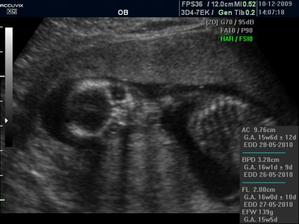

16+1 geneticka konzultace OK,nemusíme na AMC

Zaplatila jsem si ale přesto UTZ a vypada to,že budeme mit chlapečka 🙂) pry tak na 80% jistota je vždy až po porodu 🙂)

CHLAPEČEK POTVRZENY Dr Břeštákem ))